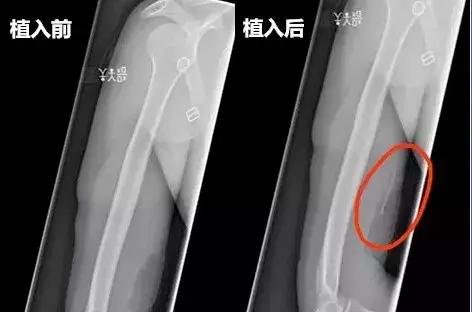

x射线下植入前后对比图

▼